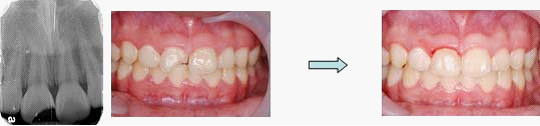

青少年小朋友常常打籃球撞傷或騎腳踏車不慎跌倒,首當其衝是門牙斷裂。家長常會驚惶失措,小朋友也會嚇到六神無主。

牙齒斷裂常有多種分類,在此不詳述。

處理原則為二大方向:

1. 如傷及牙髓神經,則應儘快保護牙髓或是直接根管治療(醫師 會依症狀判斷)

2. 是否牙齒需要固定,如需要固定時大致為輕輕力量的固定,時間約1~2週。通常牙周韌帶會癒合完全。但仍需定期觀察。